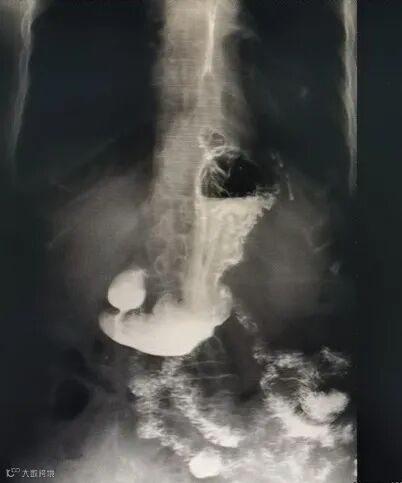

(患者影像照片)

食管裂孔疝指的是腹腔内的脏器(多数是胃)通过食管裂孔进入胸腔所导致的疾病。正常情况下,食管裂孔刚好可容纳食管通过。但如果腹腔内压力增大或食管裂孔周围结构过于松弛,腹腔内的脏器就可以通过食管裂孔进入胸腔,由此在医学上形成了食管裂孔疝。

对于无症状或裂孔较小的小疝,一般不需要特殊治疗;然而,像张女士这样裂孔较大、症状严重、药物治疗效果不佳或停药后短期复发的患者,手术往往是更为有效的治疗方式。